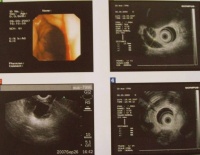

2.B超检查:反复仔细的B超检查可显示扩张的胆管梗阻的部位甚至肿瘤胆管癌的超声像可呈肿块型条索状突起型及血栓状肝内胆管癌常呈肿块或条索状肝门部癌常为条索状下部胆管癌常为突起型肝门部血栓状声像可能是肝门癌胆囊癌或转移癌由于胆管扩张发生在黄疸之前B超具有诊断早期胆管癌的价值

4.CT:胆管癌的CT基本表现为⑦显示为胆管癌之近端胆管明显扩张接近肿瘤的胆

管壁增厚于增强扫描时胆管更清晰可被强化管腔呈不规划的缩窄变形一般可发现软组织密度的肿瘤影其CT值为50Hu增强扫描时被强化CT值为60~80Hu②肿瘤多数沿胆管壁浸润性

生长胆管壁增厚边缘欠清晰增强扫描时可被强化而易显示少数呈息肉状或结节状向管腔内生长结节为软组织密度③肿瘤向腔处浸润扩展管壁边缘模糊常侵犯胆囊肝脏毗邻的血管及淋巴组织而呈不均密度软组织影形态不规整组织结构模糊界限不清